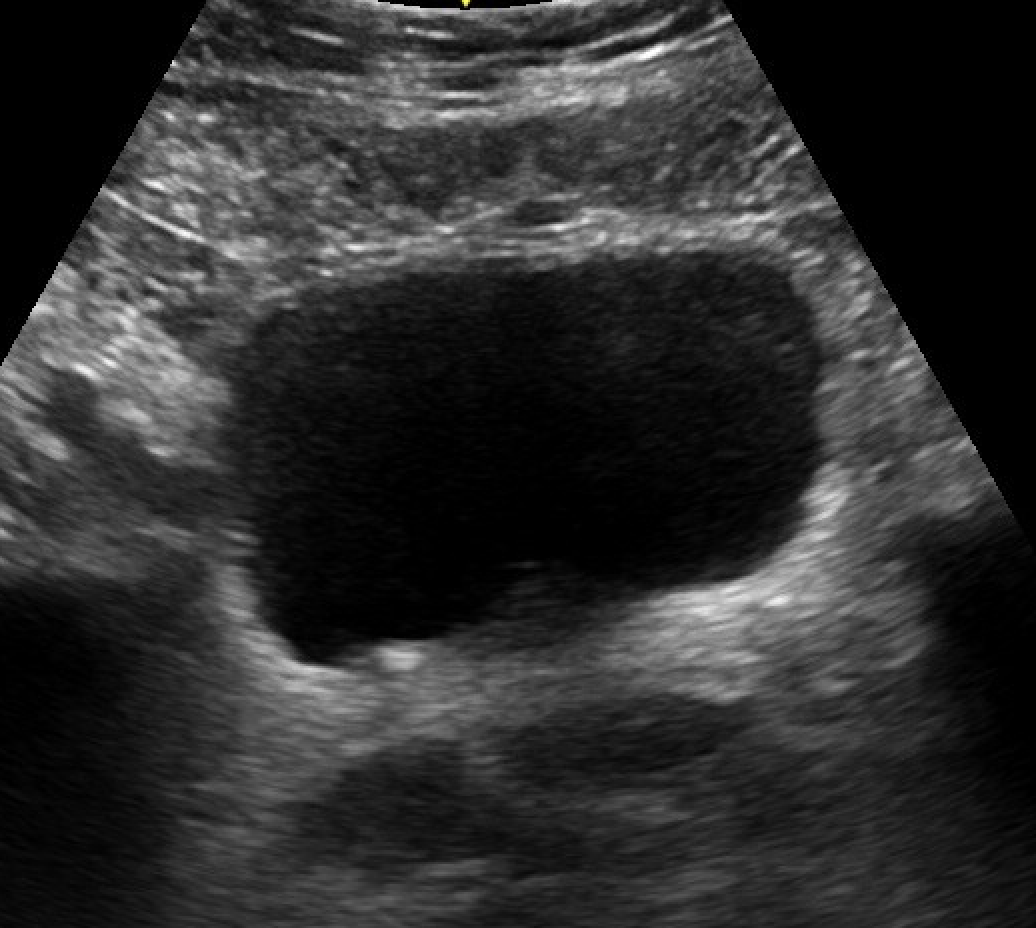

Bedside US was negative for pelvic free fluid of masses. However, renal US revealed:

R kidney (long)

This image shows grade 2 hydronephrosis: dilated renal pelvis and ureter and distended calyces. But notice the renal cortex is normal thickness. Also the calyces do not look clubbed, they maintain their normal branching structure. The left kidney was normal.

Grades of hydronephrosis: Grade 1: dilated pelvis and ureter only; Grade 2: + dilated calyces, but not clubbed; Grade 3: + clubbed cayces but normal cortical thickness >1cm; Grade 4: + thin cortex